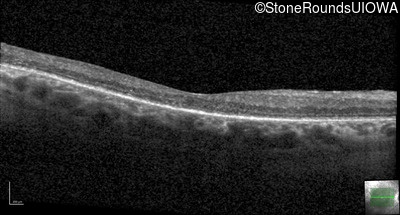

Infrared Fundus Photograph - Left - 20/30 +2

Exemplar